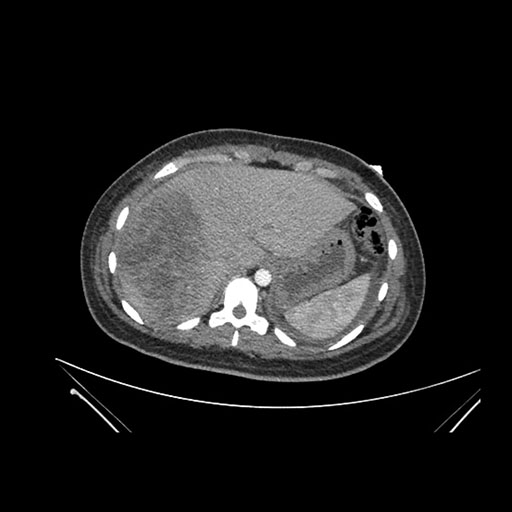

Imaging Analysis

Look through the patient's CT scan to identify any areas of concern for the necessary procedure.

Axial Venous

Based on initial findings, which issue(s) would you be most concerned about?